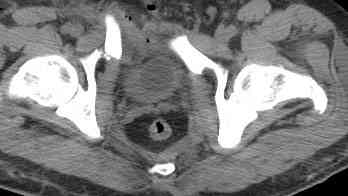

Уважаемые коллеги! опять вопрос по повреждению таза. Больной получил производственную травму 10 дней назад - удар балкой около 3 тонн в область верхней трети правого бедра и лона.

Был диагностирован перелом "типа бабочки" и повреждение уретры. Сделана цистостома. У насв отделении 3 дня. Имеется огромная флюктуирующая гематома с "галифе"-образной деформацией обеих бедер. Пнкционно эвакуировали в несколько приемов из подфасциальных полостей на бедрах около 3 литров геморрагического отделяемого с последующей эластической компрессией. При пункциях выявлено сообщение полостей на бедрах - видимо через поравннуюдиафрагму дна и полость таза - при удалении крови справа уменьшался объем левого бедра. Какой то активности проявялять покабоимся - аппаратная фиксация через отслоенные ткани представляется чреватой нагноением, открытая фиксация в условиях такой гематомы тоже не радует. Хотелось бы услышать ваше мнение

Типичная картина Morel-Lavallee повреждения.

Безуспешны многочисленные шприцевые эвакуации, мы лечим в операционной, доступом на латеральной поверхности, открытием образования с удалением и очисткой полости щеткой. Закрываем с дренажной трубкой (в архивах сайта) и накладывается мягкая повязка Спика из нескольких слоев эластичной повязки.

Следующим этапом через 5-6 дней приступаем к фиксацию повреждения таза, иначе прооперериванные на фоне Morel-Lavallee повреждения осложняются инфицированием послеоперационной раны.